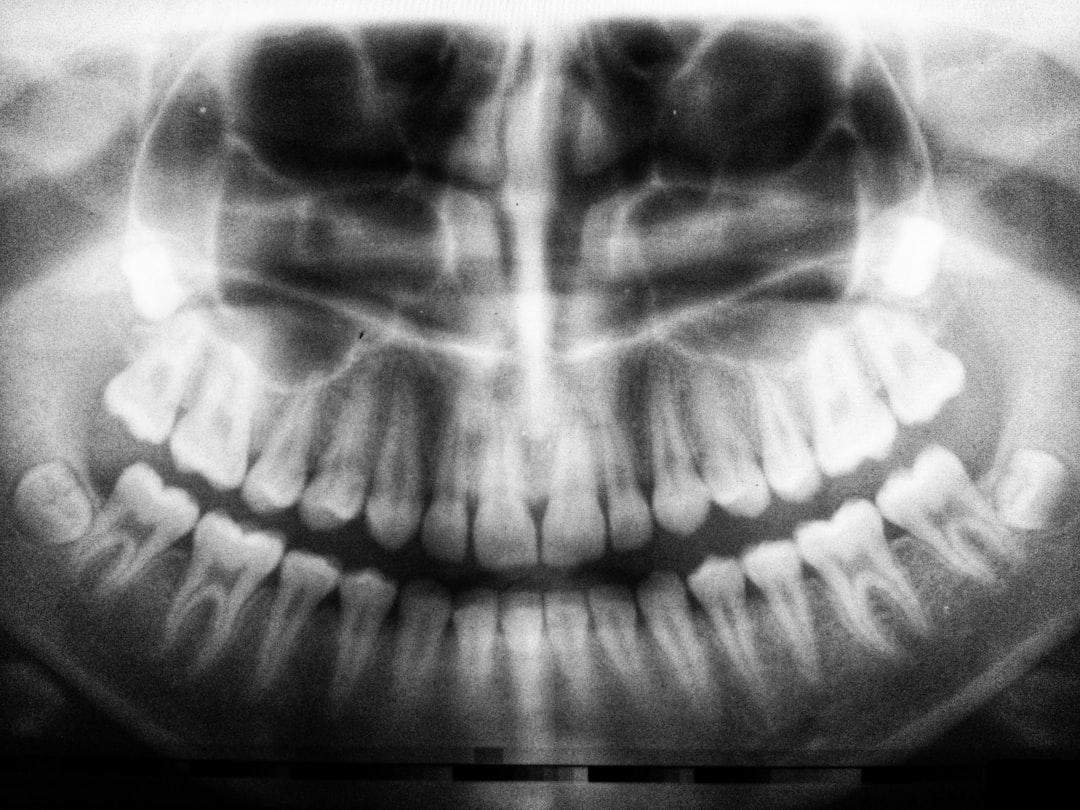

라이나 치아보험의 보장내용은 주로 예방 진료, 치료 비용, 그리고 보철 치료로 나눌 수 있습니다. 예방 진료는 정기적인 검진, 스케일링과 같은 치아 관리 활동을 포함합니다. 이러한 예방적인 조치는 치아 건강을 유지하는데 매우 중요하며, 라이나 치아보험은 이런 치료 과정에서 소요되는 비용을 보장해 줍니다.

치료 비용은 라이나 치아보험의 중요한 부분 중 하나입니다. 충치 치료, 신경 치료 등 다양한 종류의 치료가 가능합니다. 고객이 처한 상황에 따라 다르겠지만, 치료를 진행하는 과정에서 많은 금액의 비용이 발생할 수 있기 때문에, 보험의 도움은 큰 의미가 있습니다. 고객들은 이런 점에서 라이나 치아보험을 큰 신뢰를 가지고 선택하십니다.

마지막으로 보철 치료에 대한 보장도 빼놓을 수 없습니다. 크라운, 임플란트 등의 고급 치료도 포함되어 있으며, 각 치료에 대한 유연한 대처가 가능하다는 점은 이 보험의 강력한 장점으로 작용합니다. 이는 고객이 보다 나은 선택을 할 수 있도록 돕고, 결국 더 나은 치아 건강을 유지하게 만듭니다.